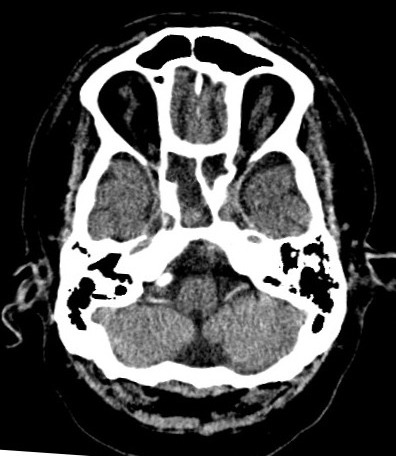

- Computed Topography – can be used for an intensive and more detailed imaging of injuries and abnormalities in the anatomical pathology (e.g. detection of pulmonary emboli or airway tumor).